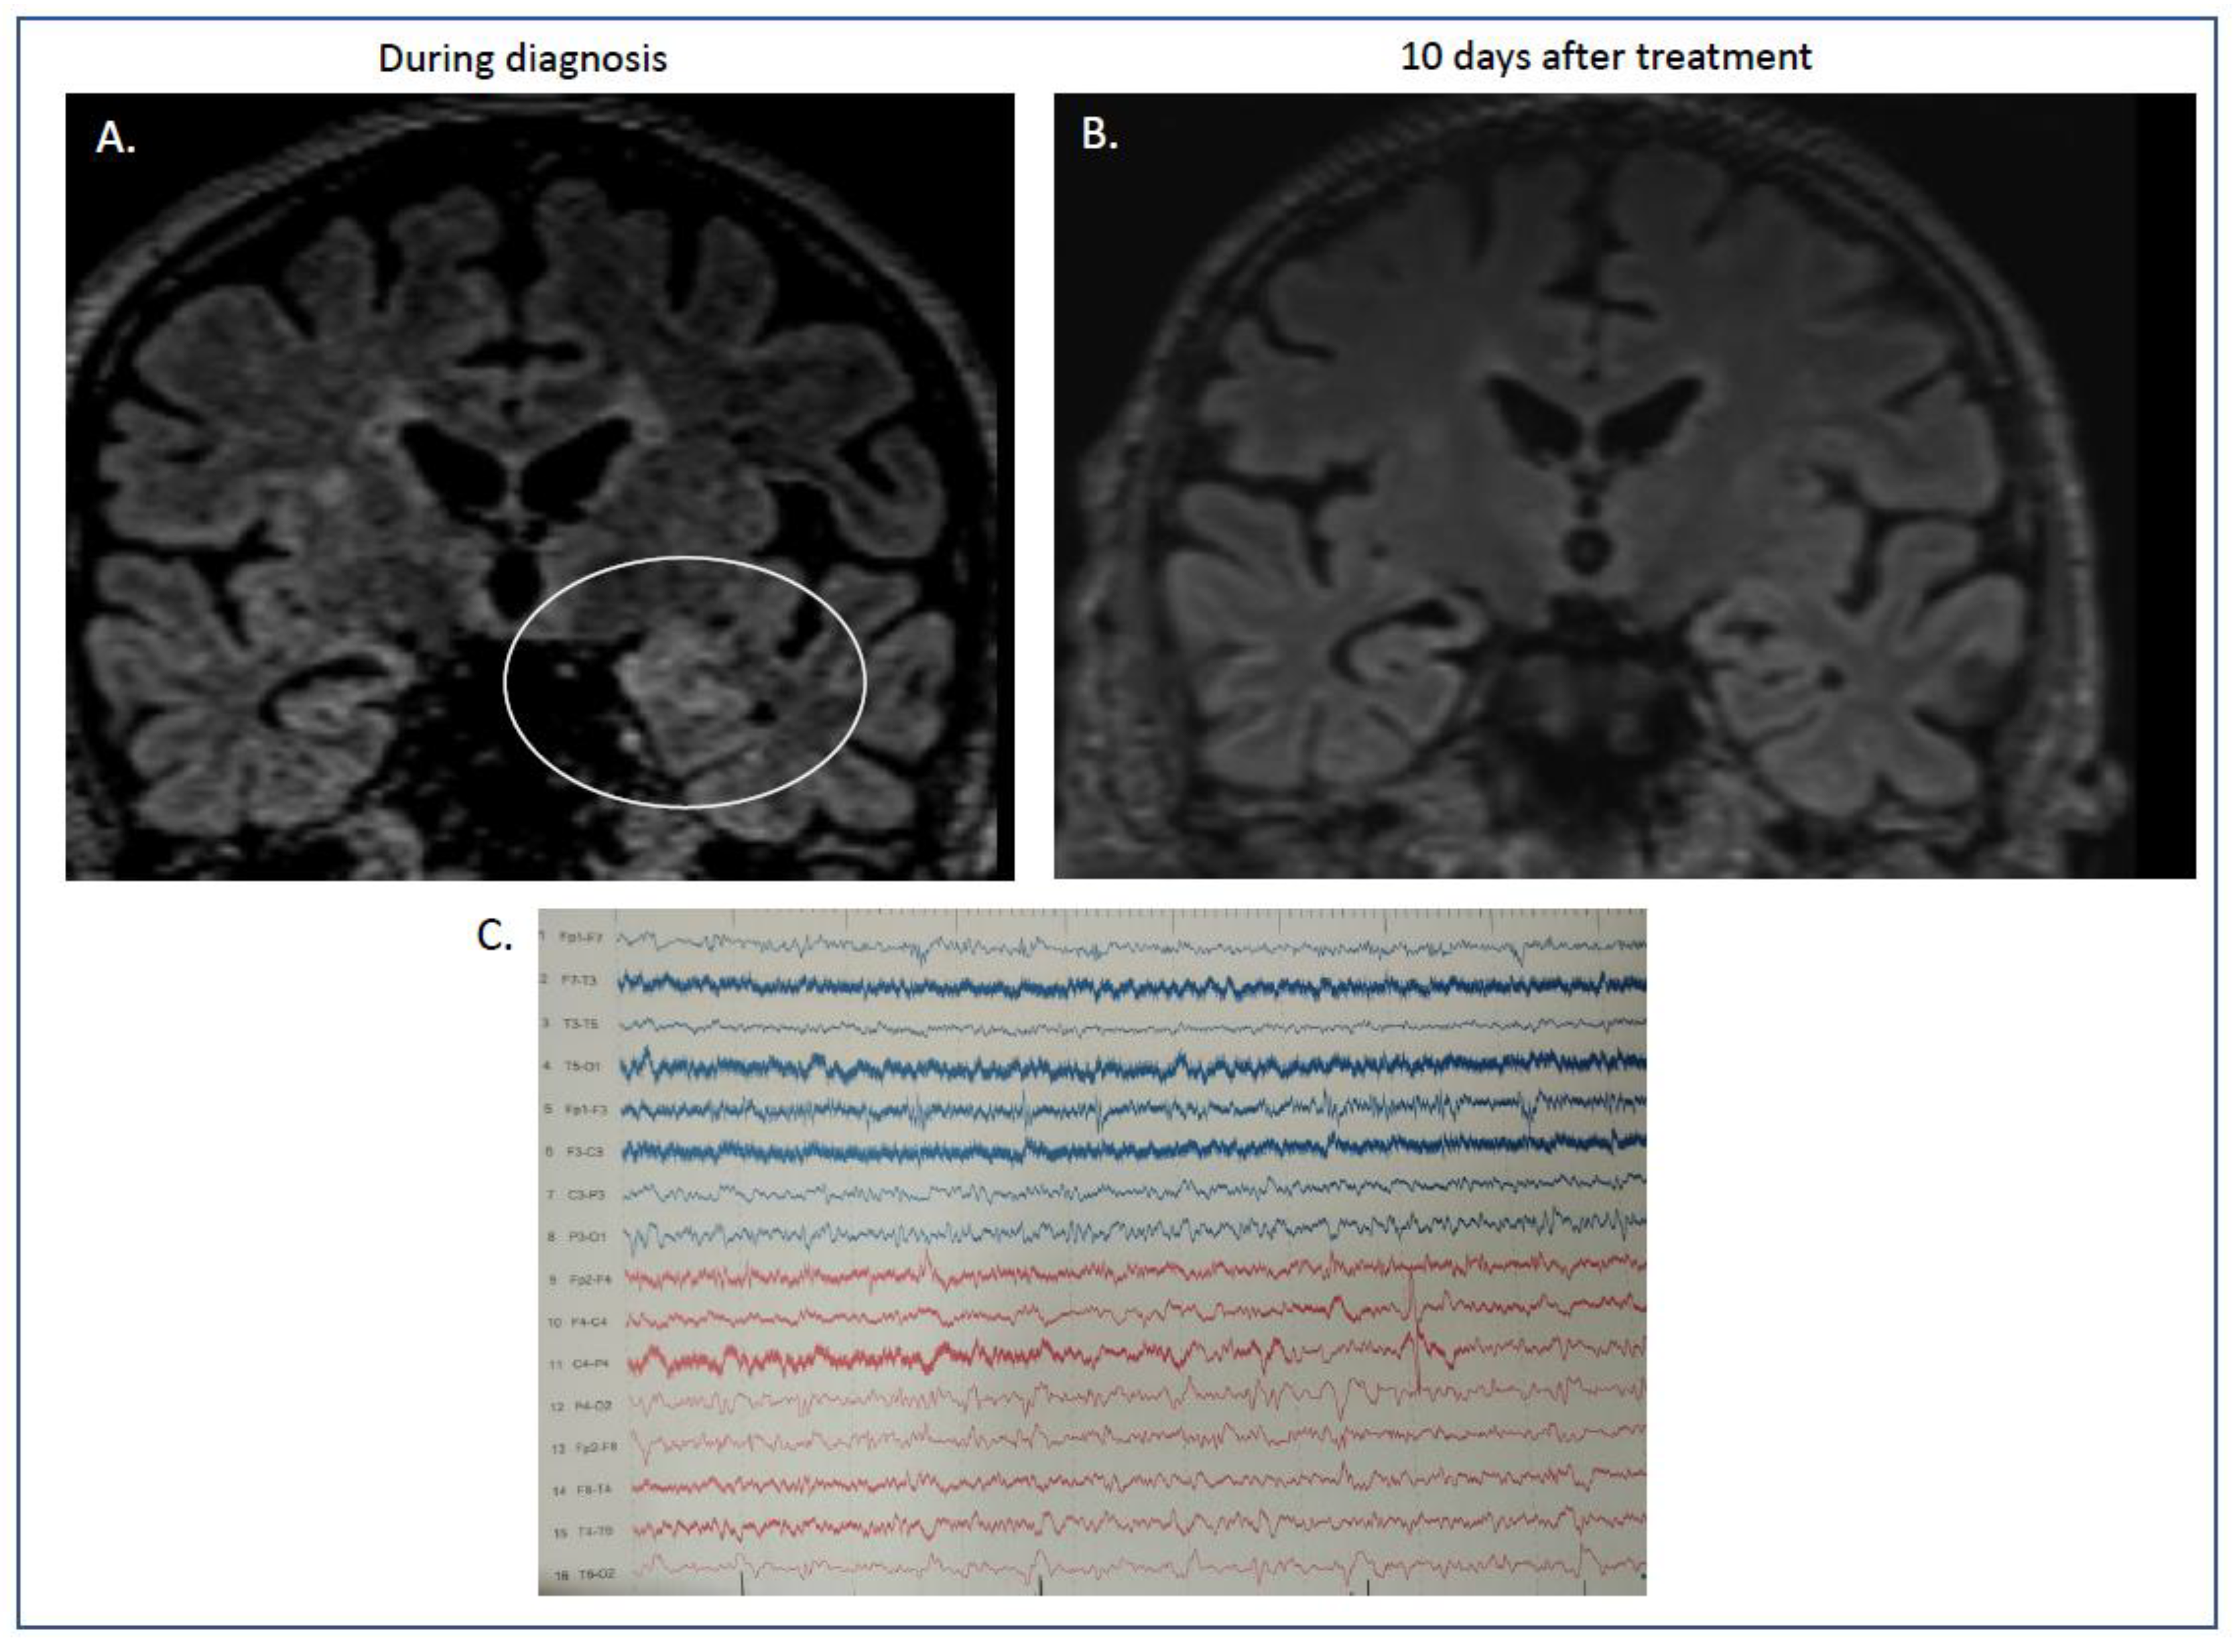

2. Case Presentation